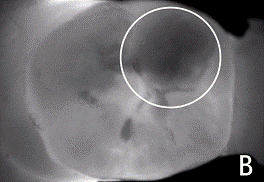

Рентгенологическое исследование. С помощью

рентгенологического метода обследования определяют скрытую кариозную полость,

ее глубину, вторичный кариес, контактный пункт или нависающие края пломбы,

соотношение пломбировочного материала, кариозной полости и полости зуба,

наличие сообщения кариозной полости с полостью зуба, степень сформированности

корней и др.

IX, Soprolife. А также современный диагностический аппарат DIAGNOcam. В основе

принципа работы DIAGNOcam лежит также метод трансиллюминации, используемый в

настоящее время в разных отраслях.

В отличие от традиционных методов, которые

обеспечивают проникновение света только через межзубные промежутки, DIAGNOcam

использует практически все структуры зуба в качестве среды для проникновения

света. Кариозные поражения блокируют этот процесс, образуя затемненные участки.

Также основное отличие от ранее предложенных на рынке диагностических приборов

это встроенная видеокамера, которая фиксирует изображение и отправляет снимки

на монитор в режиме реального времени. Свет проникает сквозь десневую и костную

ткани, позволяя получать изображения структуры ткани зуба.

Прибор позволяет визуализировать кариозные

поражения на аппроксимальных и окклюзионных поверхностях зубов. Трещины эмали и

вторичный кариес, локализованный под пломбировочным материалом, также отлично

визуализируются при условии, что пломбы не превышают определенного размера.

Программное обеспечение DIAGNOcam позволяет просматривать

снимки на экране в режиме реального времени и устанавливает соединение с сетью

и другим программным обеспечением, представленным в клинике. Снимки делаются в

любой позиции одним нажатием. DIAGNOcam обладает функцией редактирования всех

автоматически сохраняемых снимков.

Методика работы с DIAGNOcam. После регулировки

положения, прежде всего, относительно вертикальной оси, затем относительно оси

зуба, появляется четкое изображение. С помощью DIAGNOcam отчетливо

визуализируются кариозные поражения на аппроксимальных поверхностях зубов, при

клиническом осмотре их обнаружить практически невозможно (см. приложение №1).